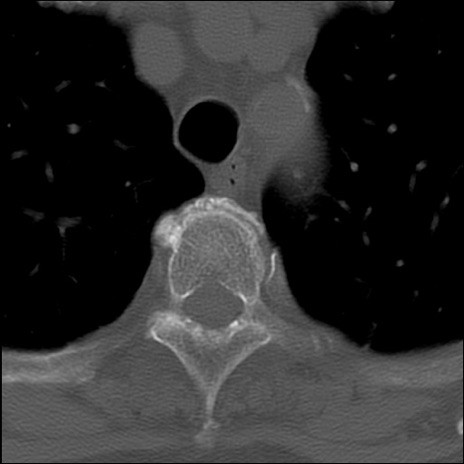

症例48 頚椎CT(横断像)

頚椎CT